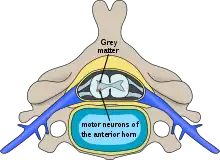

- Poliomyelitis:[1] disease caused by viral infection in the gray matter with symptoms of muscle paralysis or weakness

Most viral myelitis is acute, but the retroviruses (such as HIV and HTLV) can cause chronic myelitis. Poliomyelitis, or gray matter myelitis, is usually caused by infection of anterior horn of the spinal cord by the enteroviruses (polioviruses, enteroviruses (EV) 70 and 71, echoviruses, coxsackieviruses A and B) and the flaviviruses (West Nile, Japanese encephalitis, tick-borne encephalitis). On the other hand, transverse myelitis or leukomyelitis, or white matter myelitis, are often caused by the herpesviruses and influenza virus. It can be due to direct viral invasion or via immune mediated mechanisms.